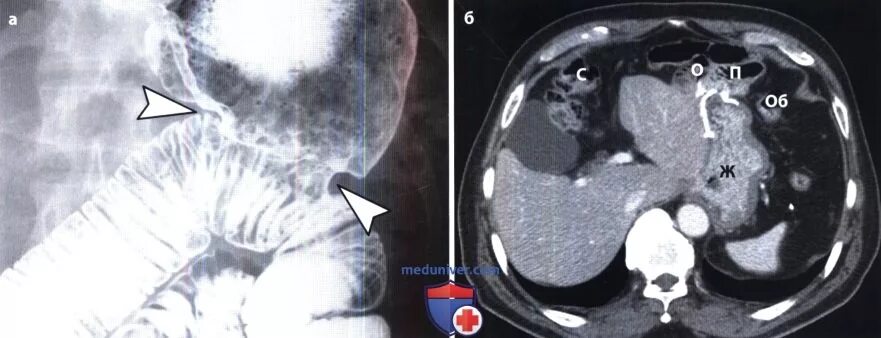

Язва желудка кт